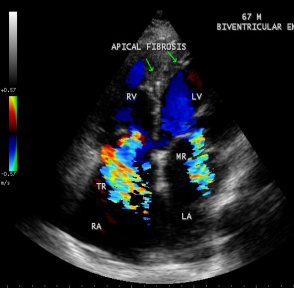

Figure 34: Biventricular EMF showing AV (atrioventricular) valve regurgitation in a 67- year old male.

Figure 35: Endomyocardial fibrosis showing thick fibrous strands in the right atrium in a 32 -year old male and a dilated right atrium

Today echocardiography is used as the screening tool at the community level as the diagnosis of EMF could be confirmed at the bedside. Echocardiography accurately assesses the pathological abnormalities of chronic disease and it is the gold standard technique for the diagnosis of EMF [36]. It reveals dense endomyocardial echocardiograms along different parts of the mural and valvular endocardium and AV valve dysfunction [37] as shown in Figures 3 to 44. The typical feature of EMF is the obliteration of trabecular portion of the ventricle and in advanced cases, there is shrinkage of the cavities creating an apical notch, regurgitation, slow flow with spontaneous echo contrast as in Figure 36 and considerable pericardial effusion. Similar to apical notch of right ventricle, a right atrial notch is well seen as contraction (or retraction) of tricuspid annulus as in Figure 40 and right atrial notch as in Figure 41 and 42, indicating the retraction of rightatrial cavity as a peculiar feature of right ventricular EMF. Biventricular enlargement as shown in Figure 40 and biatrial enlargement as in Figure 32 are the characteristic features of advanced stage of EMF. The fibrosed muscular trabeculae extending into the cavities from the walls of the chambers in the right ventricle visible as ‘cobra heads’ as in Figure 4 and in pericardial sac as in Figure 29, in the left ventricle. Aneurysmal right ventricle with scattered areas of fibrosis in the sub tricuspid region and a notch in the right atrium is well seen in a 14 –year old boy as in Figure 42 . Right atrial notch is frequently noticed in EMF patients as shown in Figure 41 in a 47- year old male with left ventricular EMF and moderate pericardial effusion.